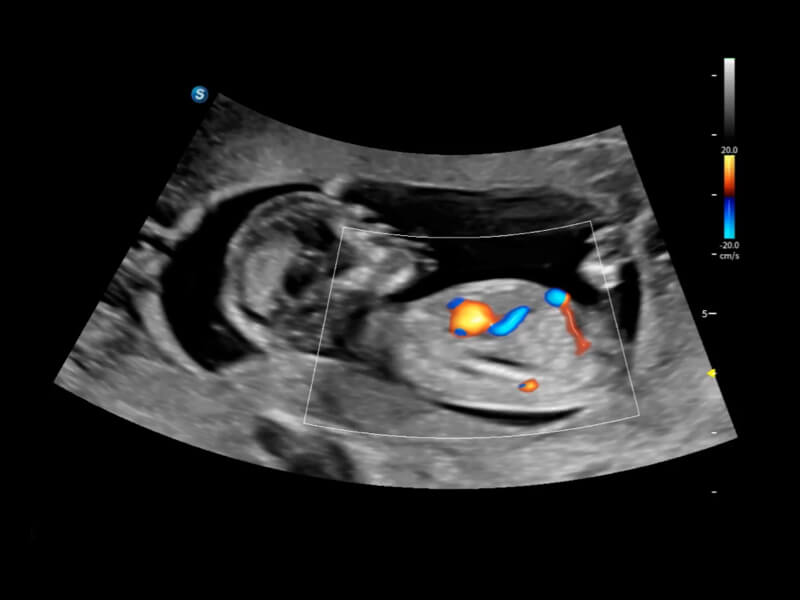

丰富的血流动力学检测技术,可在不同医疗场景中高效捕捉血流信号,助力临床诊疗。

在传统血流的基础上优化扫查和算法策略,能够更好的抑制组织信息,提炼红细胞运动信息,得到更高帧频,高灵敏度和分辨率的血流信号,还原更真实的血流动力学。